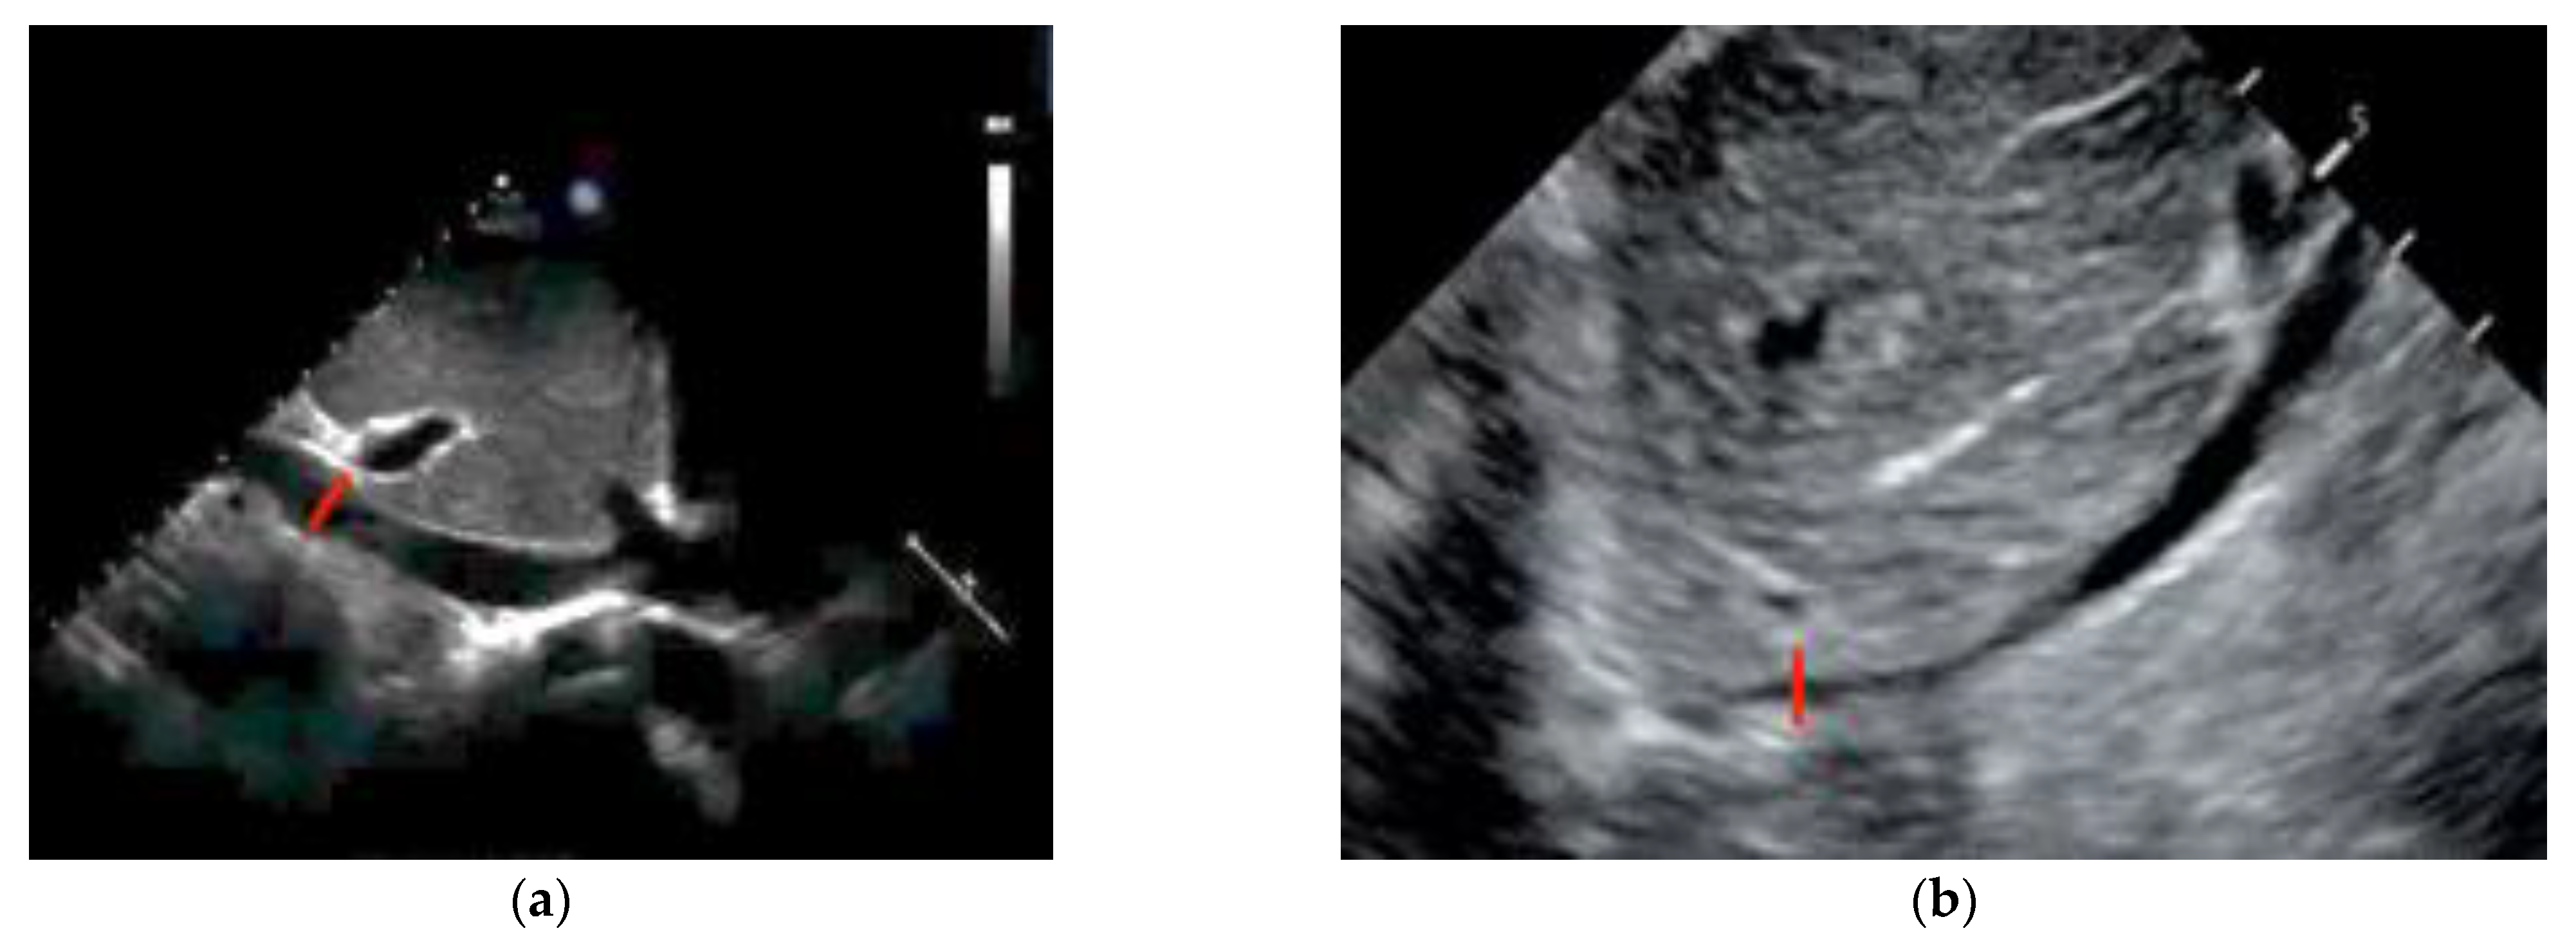

The use of sonography can help diagnose tamponade within minutes. Signs consistent with tamponade include the presence of fluid between the fibrous and serous pericardium, the collapse of the right cardiac chambers during diastole, and a small ventricular size (Figure 2; Figure 3). An exaggerated drop in systolic blood pressure due to impaired filling of the heart might also be identified with a paradoxical shift of the septum during inspiration. A dilated and poorly collapsible inferior vena cava may be observed as well [26]. Prompt intervention for tamponade can quickly address pulseless electrical activity (PEA), leading to higher survival rates compared to other causes of PEA (15% vs. 1.3%) [5,24]. In the presence of suspected or confirmed cardiac tamponade, an emergency pericardiocentesis to drain the accumulated fluid is indicated to restore circulation. The use of sonography also guides and assists with pericardiocentesis, thus enhancing the precision and safety of the procedure, with a success rate >90%. In a study evaluating the use of TTE in patients with cardiac arrest related to trauma, its utilization led to reduced time spent in the resuscitation area. Additionally, a decrease in the necessity for blood transfusions and a reduced need for invasive procedures was shown in these patients, which translated into a lower utilization of resources [27].

Figure 2.

Transthoracic echocardiography (PSLA view) showing the anechoic separation of the pericardial layers measuring 1.4 cm in diastole (arrow). (a) Right ventricle (RV) systolic collapse is shown on the left image; (b) right ventricular outflow tract diastolic collapse can be seen on the right image.

Figure 3.

Parasternal long-axis view of a pericardial effusion as indicated by the arrow. The right ventricle (RV) is not collapsed; tamponade is not diagnosed.